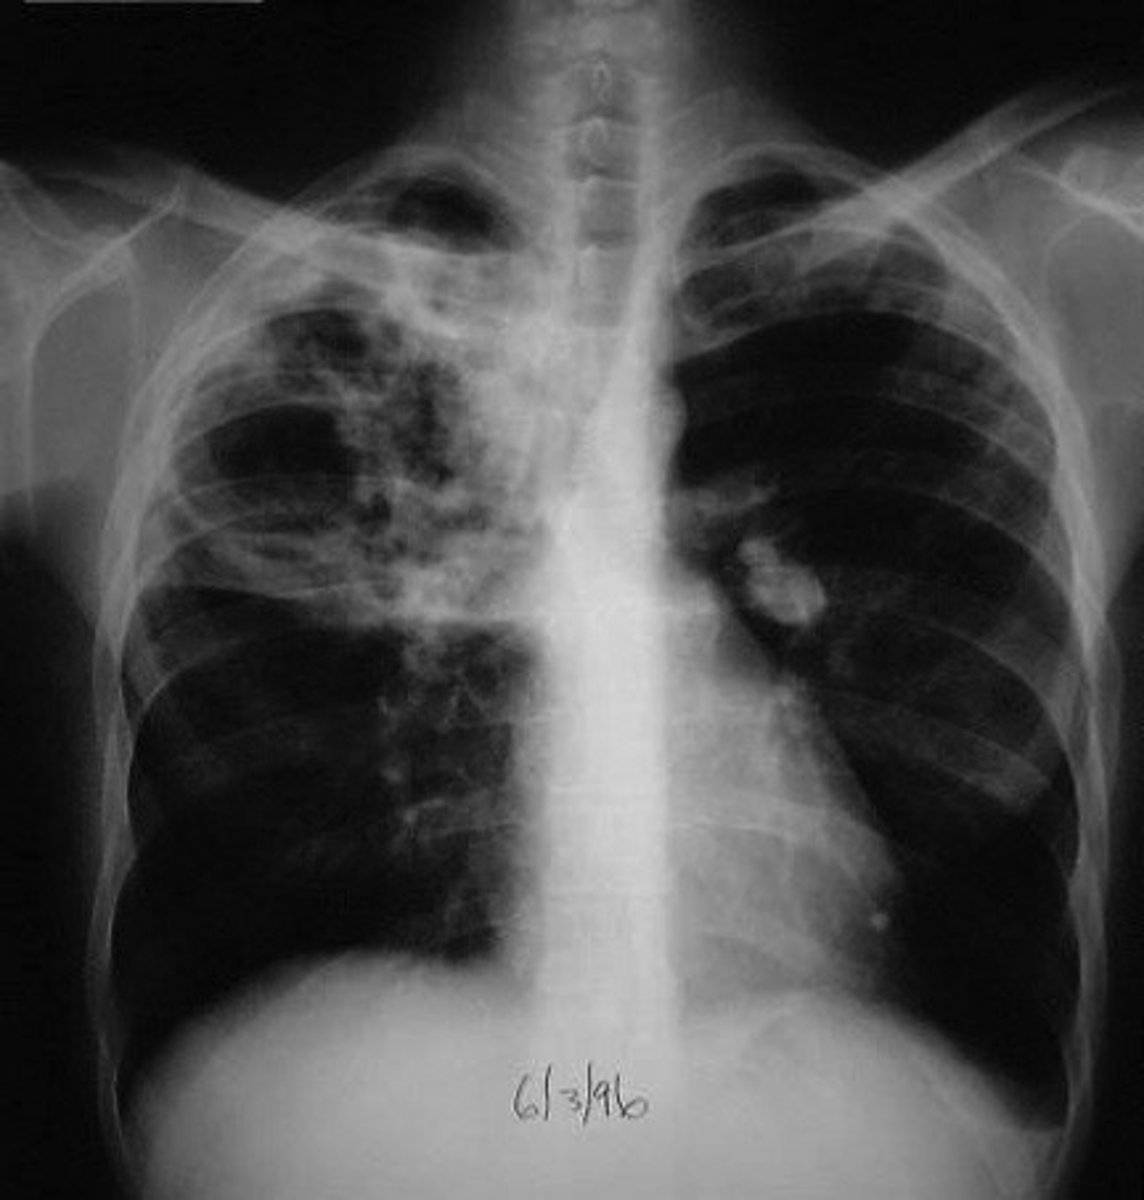

Tuberculosis

An infectious disease that may affect almost all tissues of the body, especially the lungs

am: TB is an airborne infection affecting the lungs, commonly spread through coughs and sneezes.

Effective drug treatments were developed after 1946, involving antibiotics and rest.

The emergence of drug-resistant strains of TB in the early 21st century has posed challenges, particularly in prisons and other crowded settings.

The World Health Organization initiated a global campaign against tuberculosis in the 2010s to address the increasing number of infections.